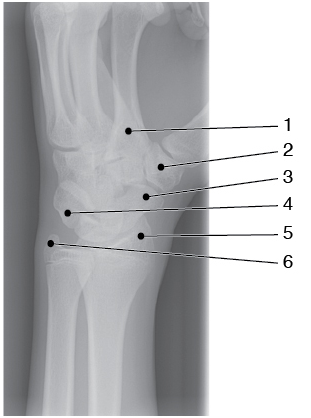

The structure indicated by 2 is the

A - Base of the 2nd metacarpal

B - Pisiform

C - Trapezium

D - Trapezoid

A

The image illustrates a semipronation oblique of the wrist. This projection best demonstrates the lateral carpals. An oblique of the proximal metacarpals and distal radius and ulna are also visualized. The base of the second metacarpal is number 1. Just lateral is seen the first carpometacarpal joint—the trapezium (lateral carpal, distal row) is labeled number 2. The scaphoid (lateral carpal, proximal row) is number 3. The pisiform is labeled number 4. The radial styloid process is number 5 and the ulnar styloid process is number 6.

What does 5 identify?

A - Trapezium

B - Scaphoid

C - Ulnar styloid

D - Radial styloid

The image illustrates a semipronation oblique of the wrist. This projection best demonstrates the lateral carpals. An oblique of the proximal metacarpals and distal radius and ulna are also visualized. The base of the second metacarpal is number 1. Just lateral, is seen the first carpometacarpal joint—the trapezium (lateral carpal, distal row) is labeled number 2. The scaphoid (lateral carpal, proximal row) is number 3. The pisiform is labeled number 4. The radial styloid process is number 5 and the ulnar styloid process is number 6.